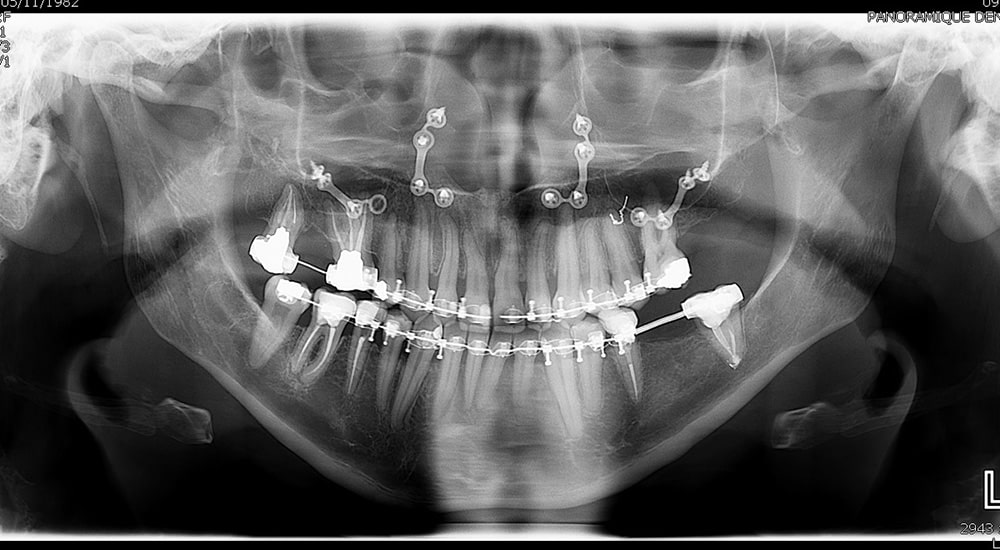

Les réhabilitations orales globales constituent très souvent un défi, tant pour le patient que pour l’ensemble de l’équipe soignante. Leur prise en charge requiert une approche pluridisciplinaire, impliquant une collaboration étroite entre l’omnipraticien et différents spécialistes, notamment en orthodontie, chirurgie maxillo-faciale, endodontie et implantologie.

Le flux numérique améliore la communication entre le praticien, le prothésiste et le patient tout en garantissant un résultat prévisible....